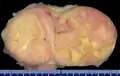

Gross pathology of an atypical solitary fibrous tumor, evidenced by some deeply yellow necrotic areas